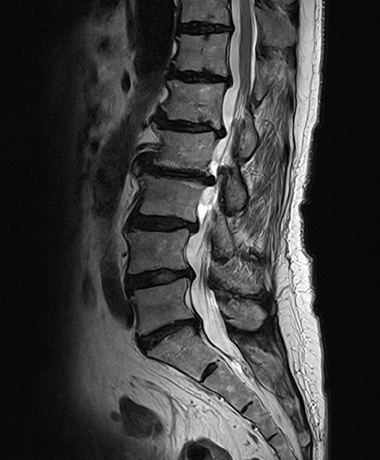

<h3>정확한 진단은 선명한 영상에서 시작됩니다</h3>

<div class="name">1.5T</div>

<div class="name">그린몰 3.0T</div>

<li>미세한 신경·인대·근육 등 연부조직까지 정밀한 촬영</li>

<li>선명한 해상도로 통증의 원인 및 미세 병변을 정확히 구분</li>

정확한 진단은 선명한 영상에서 시작됩니다

1.5T -

그린몰 3.0T

- 미세한 신경·인대·근육 등 연부조직까지 정밀한 촬영

- 선명한 해상도로 통증의 원인 및 미세 병변을 정확히 구분